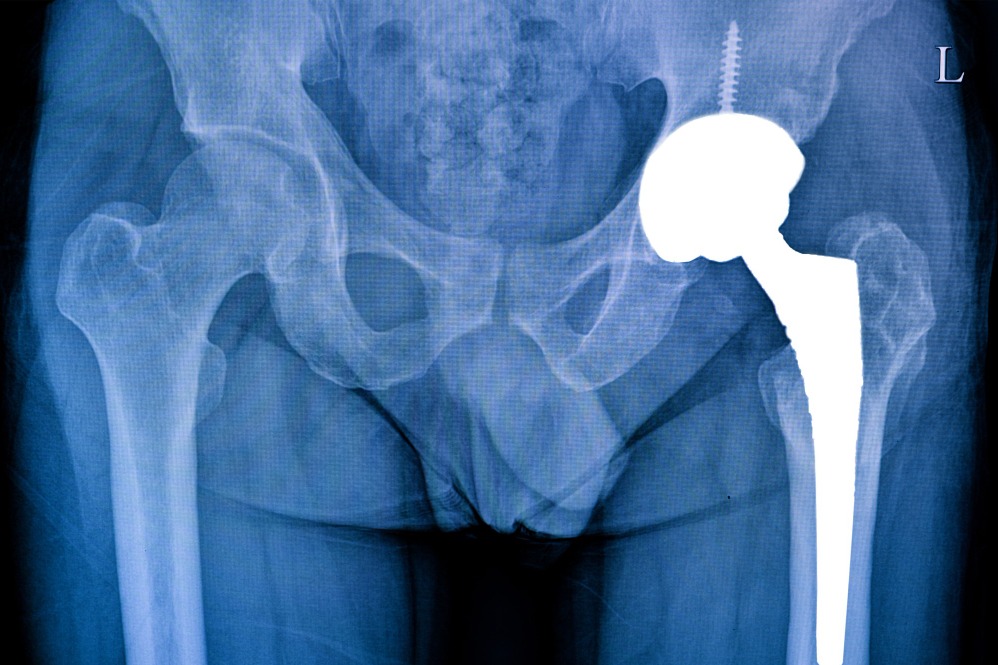

Best Surgeon for Partial Hip Replacement in Tardeo Supporting Joint Stability

Hip discomfort often starts as mild stiffness and gradually affects walking balance. Dr. Sujit Korday in Tardeo frequently evaluates patients who noticed changes in movement but waited too long to seek care. Partial hip replacement is considered when damage is limited to a specific area of the joint.

This procedure preserves healthy bone while replacing only the affected portion, allowing for natural movement patterns. Proper assessment ensures that partial replacement is appropriate, as not all cases benefit from this approach.